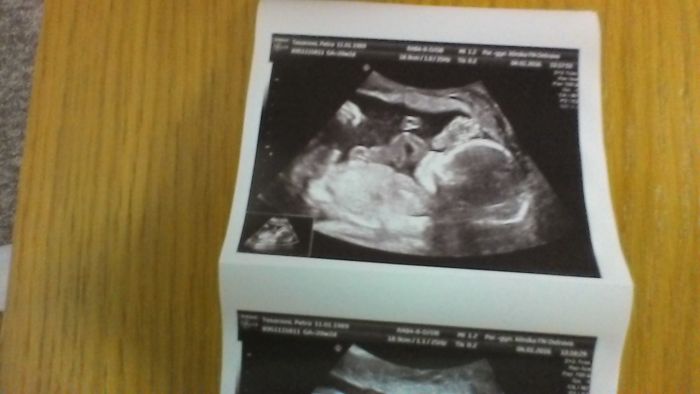

Dupi, krásnej obrázek, takovej hezky kontrastní :-)

Holky nádherné fotecky..Evi já také nemůžu spát pořád se budim a brzo ráno jsem vyspala.. vadí mi to teda dost...Berdo oboje znám jak Hvězdu Sarku..mohly by jsme se sejít. To by bylo fajn..Jinak já dnes v poradne ok..dělal mi teda jen utz. Tam vše vpohodě. Mimco se tam mrskalo..pohlaví nevím. Bylo na boku..